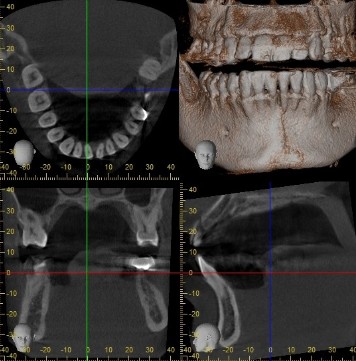

「歯科用CT」

「CT画像」